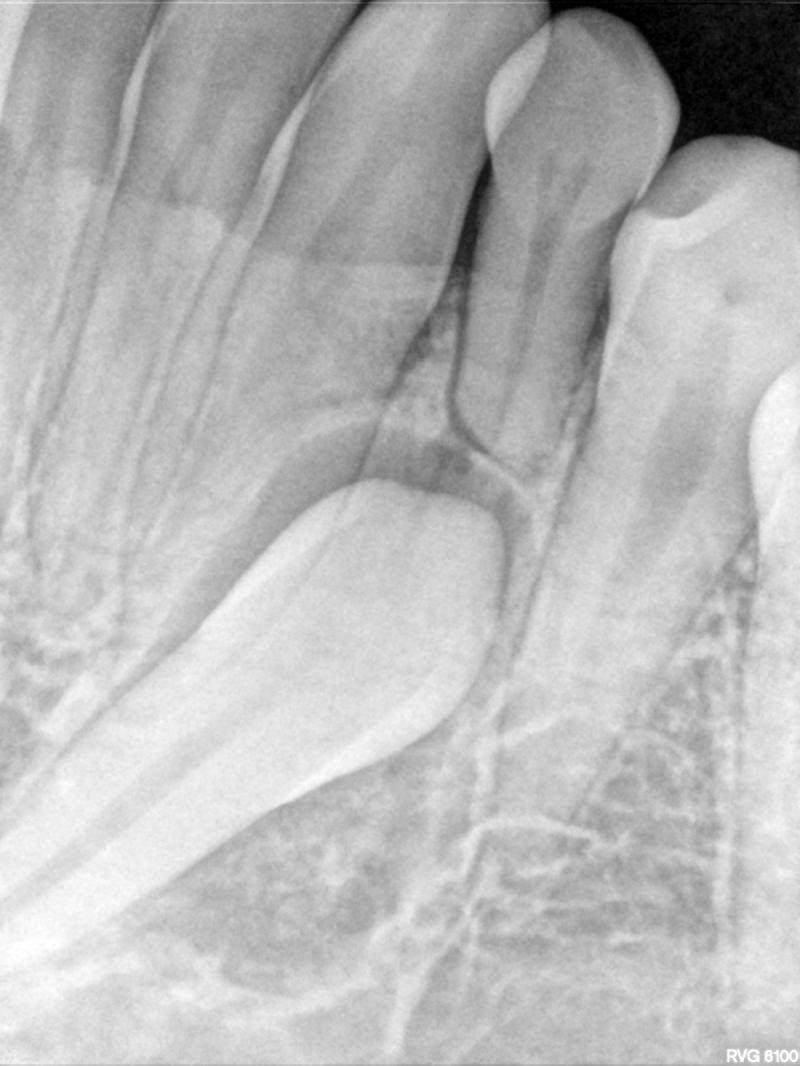

Fig. 14 Periapical radiograph of impacted lower left canine (at 15 y.o., 1 year prior to starting ortho)

© Copyright 2007-2014, Vu Orthodontics. All rights reserved.